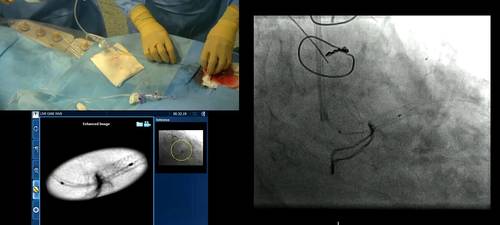

Live case transmission from Madrid – IVUS guided PCI

Dr Javier Escaned and his team demonstrate the use of IVUS in vessel evaluation pre and post stent implantation.

• Live case demonstrations using IVUS co-registration